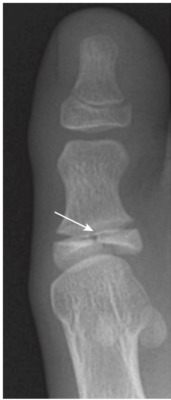

- Gãy Jones là một gãy ngang của xương bàn đốt chân ngón út cách nền xương khoảng 1 đến 2 cm, do gập lòng bàn chân và cổ chân vẹo trong. Gãy xương Jones thường lâu lành hơn so với gãy bong mảnh bám nền xương bàn đốt ngón chân út (là loại gãy thường gặp hơn, dancer’s fracture) (Hình 12).